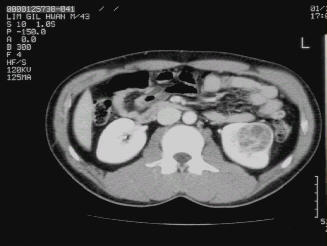

○ 복부전산화단층촬영(CT scan)

신종물의 평가에 가장 중요한 검사로, 혈관, 국소림프절 및 주위장기 전이유무를 판단하여 임상적 병기 결정하게 됩니다.

그림 3. 큰 우측 신세포암의 전산화단층촬영사진